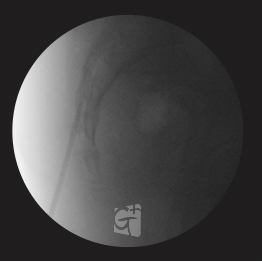

요추 관절 치료

요추관절 공간에 정밀하게 약물주입